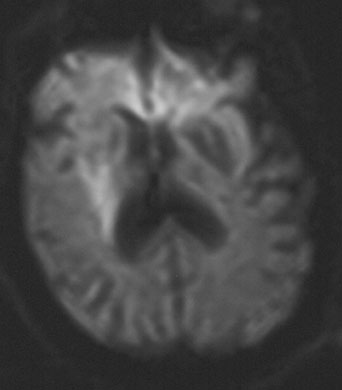

As diffusion-perfusion MRI and other techniques to quantify blood flow, such as perfusion CT and xenon-CT, become more widely available, clinicians will be better equipped to estimate the relative benefits and risks of thrombolysis, based more on physiologic data than rigid time constraints. Patients with large areas of penumbra tissue would benefit most, while those with large tissue volume with blood flow under 10 mL per 100 g/min would not benefit and may be at increased risk for hemorrhage. A recent report utilizing diffusion-perfusion MRI to guide thrombolysis with desmoteplase allowed the safe and apparently efficacious administration of this thrombolytic agent up to 9 hours after the onset of ischemia.45 Figure 1 exemplifies the use of diffusion-perfusion MRI in acute stroke treatment. Ideally, multimodal testing of the parenchyma to exclude hemorrhage, a viability study to determine the amount of salvageable brain, and a vascular study to assess vessel patency would provide the clinician with the information to make rational decisions regarding the need to treat. Magnetic resonance (MRI, diffusion-perfusion imaging, and magnetic resonance angiography [MRA]) and CT technology (with CT perfusion and CT angiography) have the potential to guide this multimodal evaluation.

Fig. 1. An 81-year-old man with atrial fibrillation developed acute onset of left-sided weakness and presented to hospital 3 hours and 40 minutes after onset of symptoms. A: The diffusion-sequence magnetic resonance imaging (MRI), with infracted tissue in the right basal ganglia in white. B: Decreased perfusion in the right middle cerebral artery distribution (white area). Given the relatively small diffusion abnormality and the large perfusion defect, it was decided to proceed with thrombolysis despite the time elapsed.